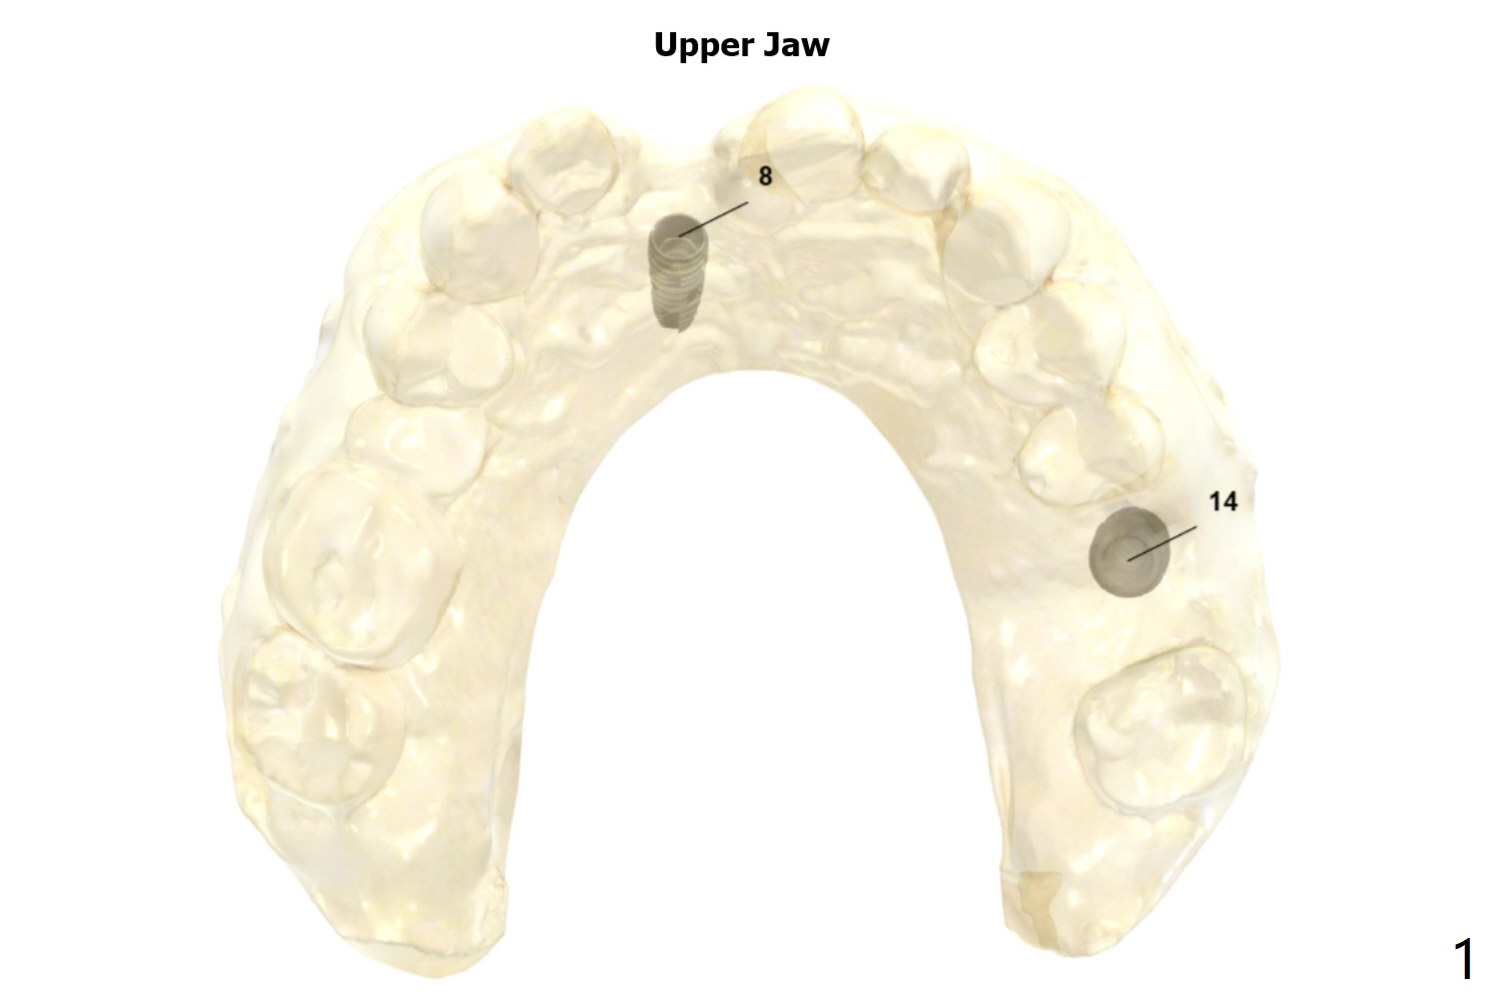

Narrow Implant with Angled Abutment

Return to Upper Incisor Molar Immediate Implant, Trajectory Protect Graft